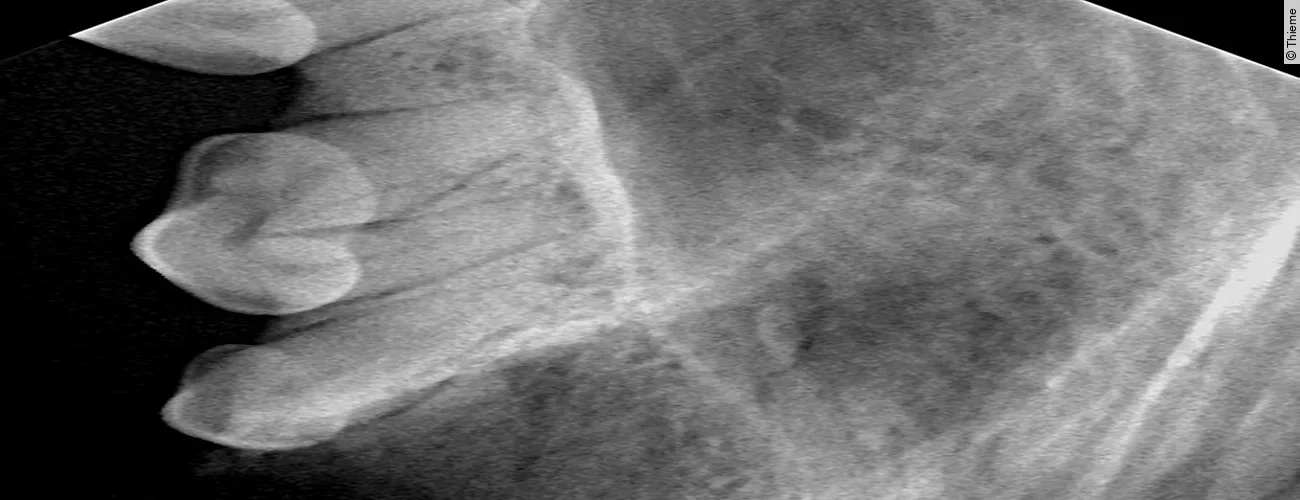

Replantation nach Avulsion Oberkieferfangzahn rechts

Der Originalartikel „Avulsion Oberkieferfangzahn rechts“ stammt aus dem Bild-Atlas der Zahnbehandlungen Hund und Katze; 2. aktualisierte Auflage; 2022.